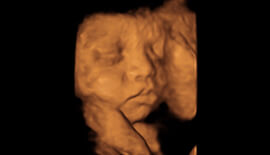

4D超音波外来

当院では妊娠健診中に妊娠週数を指定して、胎児超音波検査と4D超音波を行っています。普段の妊娠健診中の超音波検査より詳しく検査を行います。ただ、それだけ詳しく検査をしても、すべての異常を発見することはできませんが、妊娠中に胎児異常がわかっていれば生まれてくる赤ちゃんに早くから最善の対応をできることがあります。

・必ず妊娠健診を一緒に受診していただきます。(4Dだけの予約は不可)

・いつもよりゆっくり、お腹の中の赤ちゃんの様子をご覧いただけます。

・付添は可能です。

・お土産に画像データ(JPEG形式)をCD-ROMに記録してお渡ししています。

- 4D超音波とは

- 立体画像(3D・静止画)に時間要素を加えることで、

動く立体画像(4D)になります。

ただし、赤ちゃんの向きやポーズ、 羊水量など条件が

揃わないとお顔などを描出することができません。